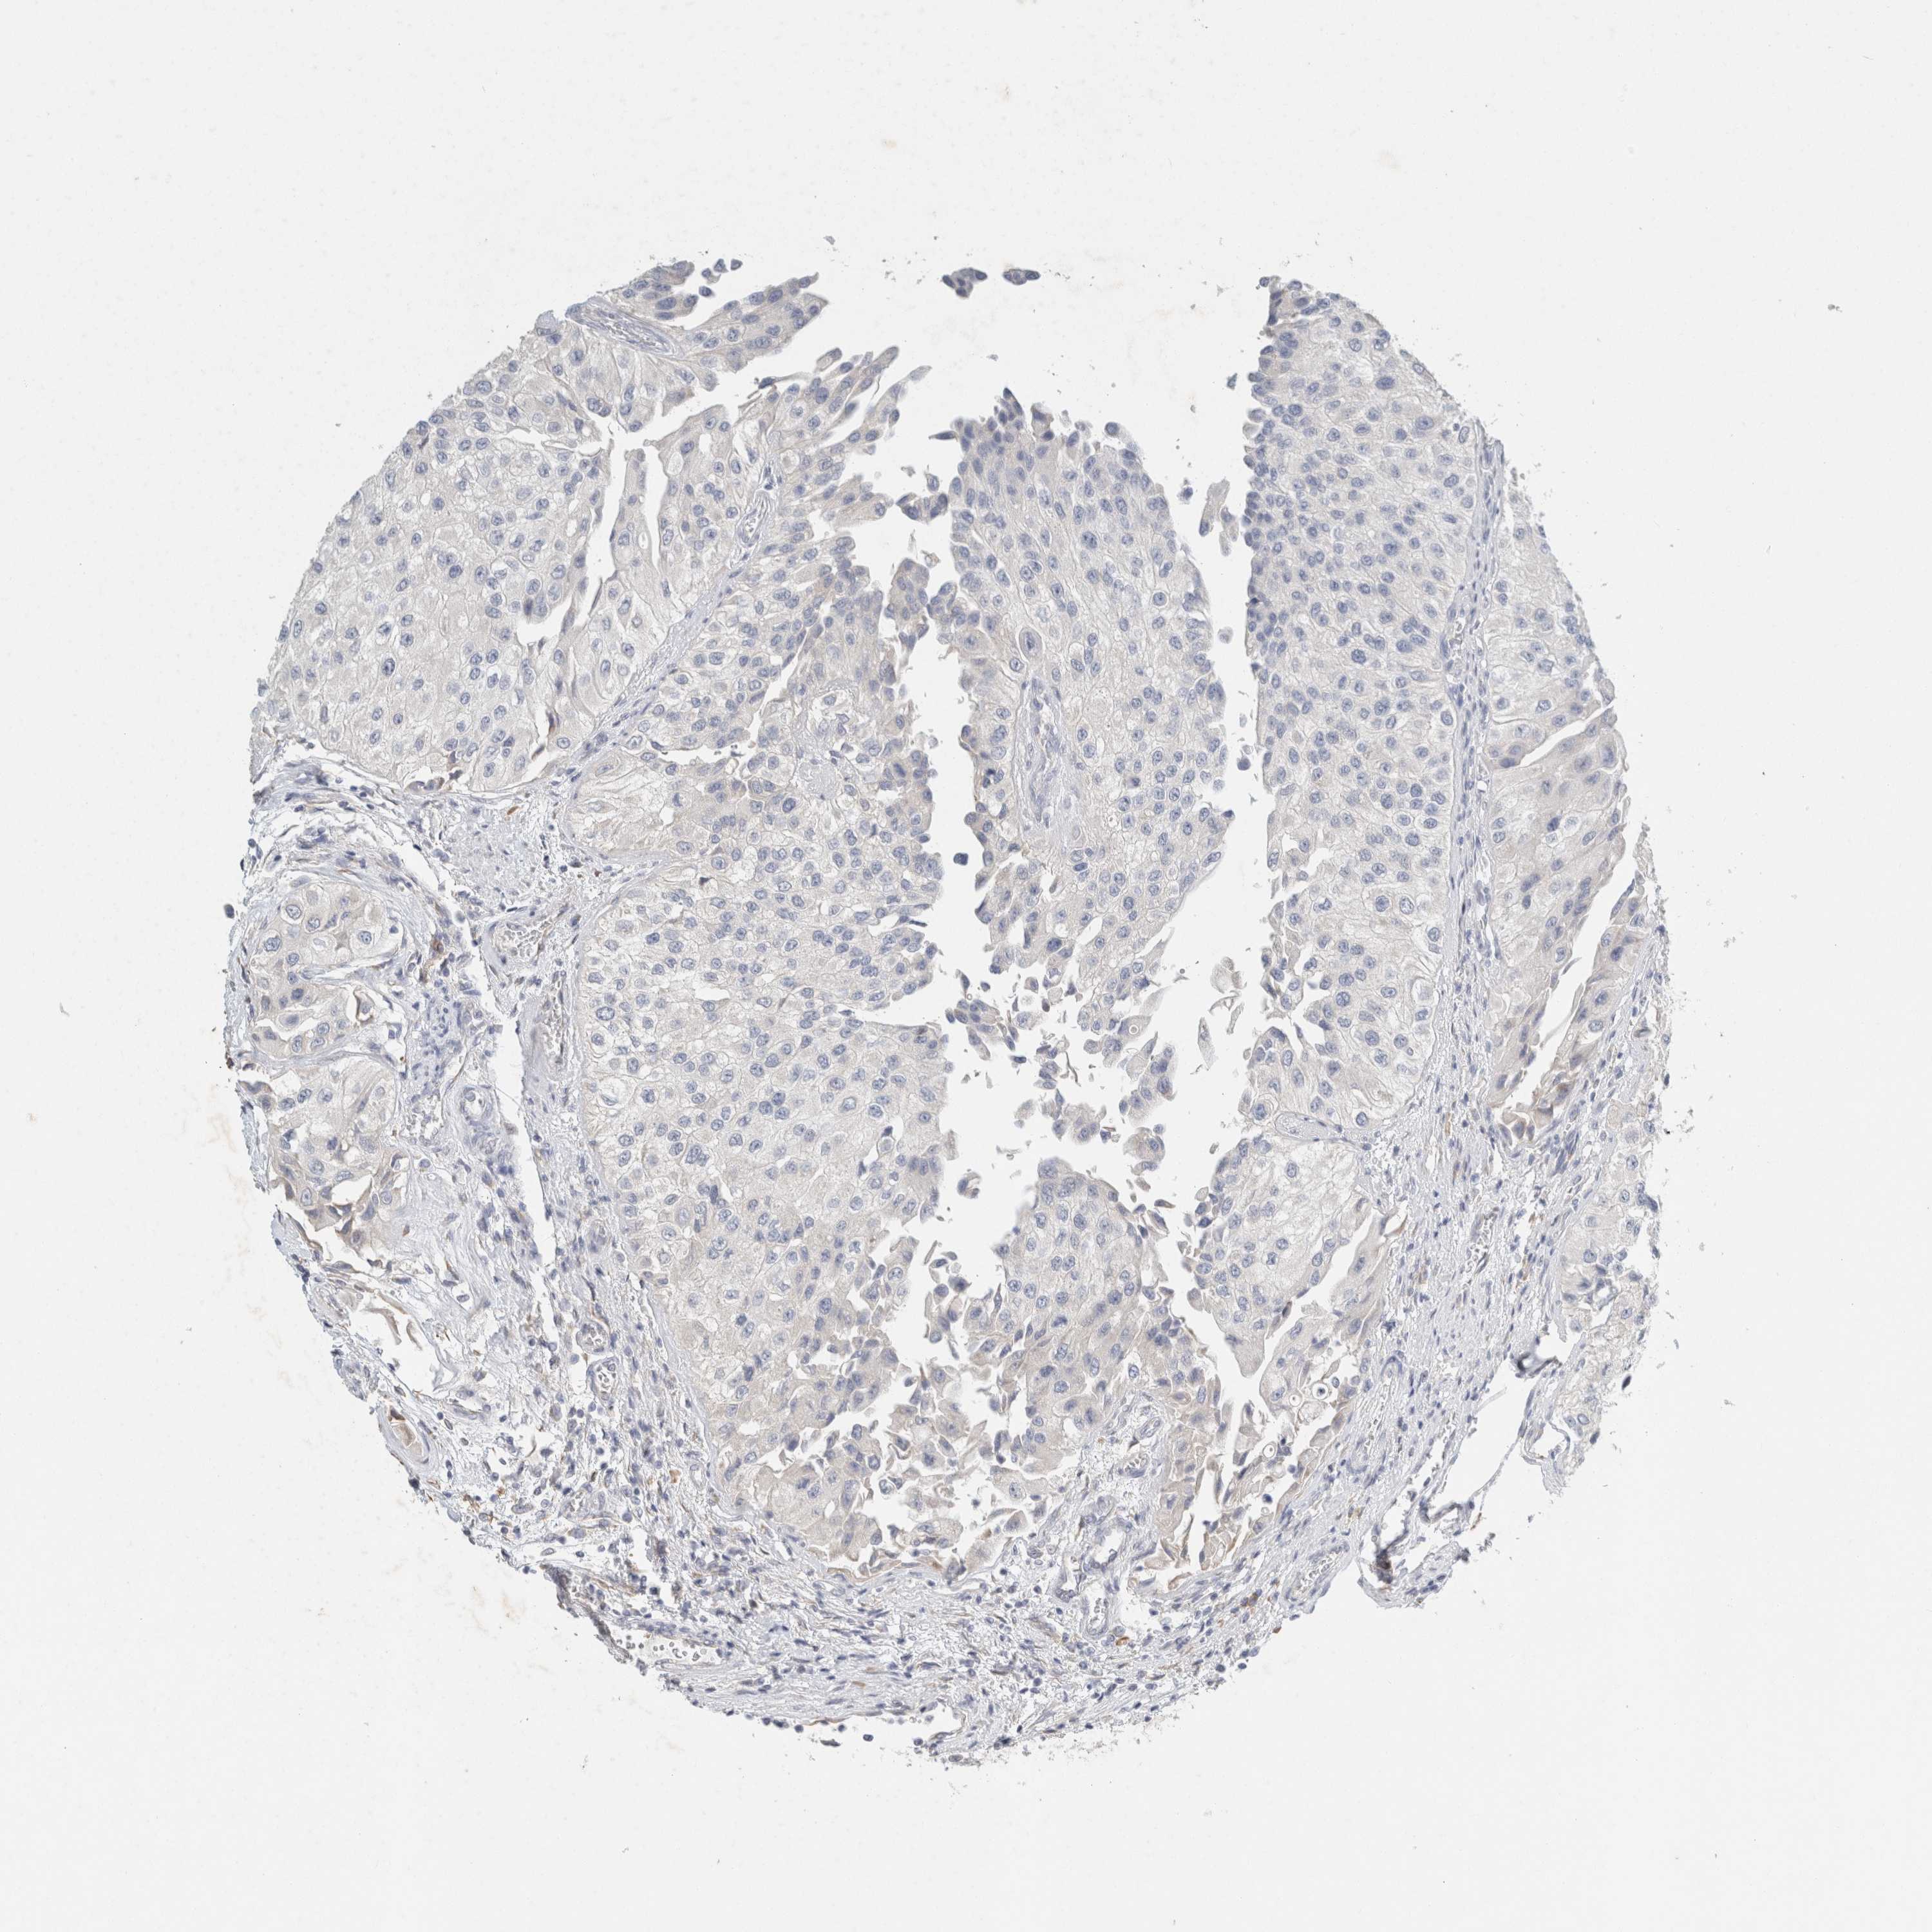

UROTHELIAL CANCER - Protein expressioni

A mouse-over function shows sample information and annotation data. Click on an image to view it in a full screen mode. Samples can be filtered based on level of antibody staining by selecting one or several of the following categories: high, medium, low and not detected. The assay and annotation is described here.

Note that samples used for immunohistochemistry by the Human Protein Atlas do not correspond to samples in the TCGA dataset.

Antibody stainingi

Antibody staining in the annotated cell types in the current human tissue is reported as not detected, low, medium, or high, based on conventional immunohistochemistry profiling in selected tissues. This score is based on the combination of the staining intensity and fraction of stained cells.

Each image is clickable and will lead to virtual microscopy that enables deeper exploration of all samples and also displays staining intensity scores, fraction scores and subcellular localization as well as patient and tissue information for each sample.

Antibody HPA022845

Antibody HPA023138

Antibody CAB010900

Antibody CAB012976

Urothelial carcinoma, Low grade

Urothelial carcinoma, High grade